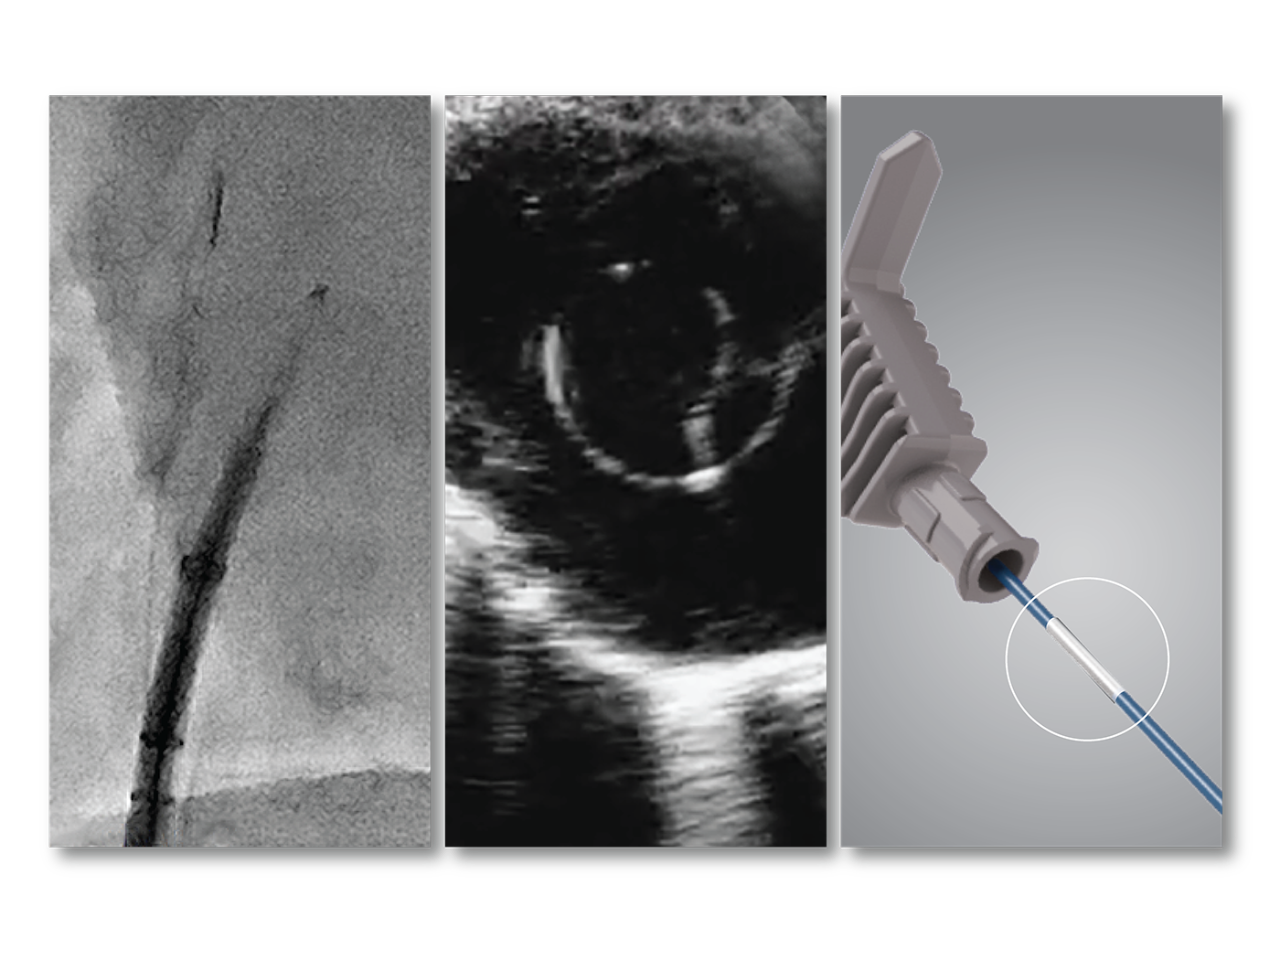

Know where you are at all times with OMNIviz technology

Reliably locate the VersaCross Connect solution on fluoroscopy and ultrasound. Positional markers indicate position of RF tip within dilator. Connect to DuoMode Cable to track and mark RF tip on mapping system.

Fluoroscopic image of RF wire in sheath/dilator assembly.